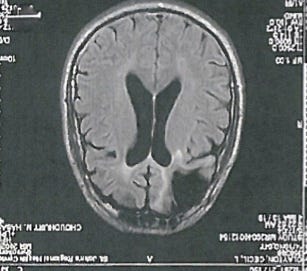

The scan of Clayton’s brain. Photograph: Supplied

Also here in Missouri, Cecil Clayton (74) faces execution on Tuesday, March 17. In 1996 Clayton killed Deputy Christopher Castetter by shooting him in the head. According to Clayton's lawyers, six psychiatric evaluations call into question whether he should be regarded as mentally competent enough to be executed by the state. Not only does Clayton have dementia and a low I.Q. of 71, but in 1972 he suffered a serious head trauma when a piece of lumber flew off a circular saw blade, struck him in the forehead, and required the removal of a significant portion of the frontal lobe of his brain. A number of studies, as shared in Adrian Raine's The Anatomy of Violence: The Biological Roots of Crime, find correlations between brain injury and violent crime. This raises the question about the perpetrator's culpability.